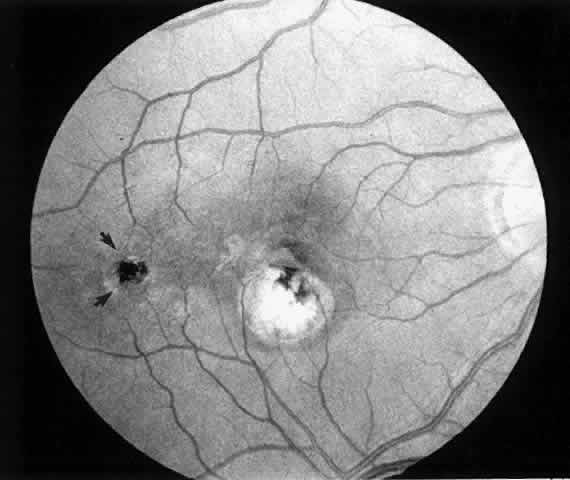

In January 1991, Thomas and Kaplan14 reported an alternative approach to subfoveal neovascularization in POHS. Instead of a large flap retinotomy, their technique employed a small retinal hole through which instruments were introduced into the subretinal space. The neovascular membrane was dislodged, grasped with forceps, and extracted through the slightly enlarged retinotomy. An air-fluid exchange was followed by endolaser burns around the retinotomy and short-term tamponade with sulfur hexafluoride gas. In the first two POHS cases, visual acuity improved dramatically (from 20/400 [6/120] to 20/20 [6/6] in one case and 20/400 [6/120] to 20/40 [6/12] in the second). These early encouraging results prompted refinement of the instrumentation and surgical technique and their application in a wider variety of cases.15

In most cases that meet the criteria for subretinal surgery, the edge of the neovascular complex can be readily visualized under the operating microscope without angiography. In some relatively recent membranes, even if they are anterior to the RPE, we have found the edges to be more difficult to discern. Thus, on occasion, it is helpful to select a frame from the preoperative fluorescein angiogram to project on a screen in the operating room. The image is inverted and reversed to match the surgeon's view through the operating microscope at the top of the patient's head.

Besides being in the most advantageous location, the retinotomy should be as small as possible. Initially, we lightly diathermized the surface of the retina and then used the myringotomy blade to tease open a small hole through which an angled infusion needle was introduced.15 At the suggestion of Lambert and co-workers at Emory University, we stopped using diathermy. We now use a 120° angled, sharply pointed 36-gauge subretinal pick to pierce undiathermized neurosensory retina (Fig. 2). Occasional slight retinal hemorrhage can be controlled by transiently increasing the intraocular pressure. After the tiny hole has been made, the surgeon introduces the angled 33-gauge infusion needle beneath the retina and the assistant gently infuses balanced salt solution to elevate the neurosensory retina. This is accomplished by pushing on the plunger of a syringe that is connected to the hub of the needle by a short piece of tubing. As the fluid enters the subretinal space, attention is directed to edges of laser scars and/or adhesions to the underlying membrane (Fig. 3). Excessive infusion pressure can easily tear the retina. If areas of retina remain adherent, the infusion is stopped and the tip of an angled subretinal pick is carefully passed over the anterior surface of the membrane surface to break any residual adhesions. In a similar manner, the tip of the angled subretinal pick can be used to gently separate the thinned retina from an underlying photocoagulation scar. Occasionally, horizontal subretinal scissors are necessary to cut firm adhesions. These scissors have a similar 130° bend and blades approximately 3 mm in length to allow manipulation through an eccentric retinotomy. Trauma to foveal photoreceptors from either the pick or scissors is carefully avoided. If the retina is not mobilized over the entire photocoagulation scar, separation is achieved at least far enough into the scar to allow manipulation and extraction of the membrane without tearing the adjacent retina. The sharp tip of the angled subretinal pick is used to elevate the edge of the neovascular complex from the underlying RPE (Fig. 4). Care is taken to swing the pick in a pivoting or rotating manner to stretch or enlarge the retinotomy as little as possible. This requires close attention not only to the primary site of action at the membrane but also to the instrument shaft at the retinotomy site. In the appropriate cases, the complex dislodges easily from the underlying subfoveal RPE but remains attached to the edge of a laser scar (in recurrent cases) or to the stalk of choroidal vascular ingrowth.